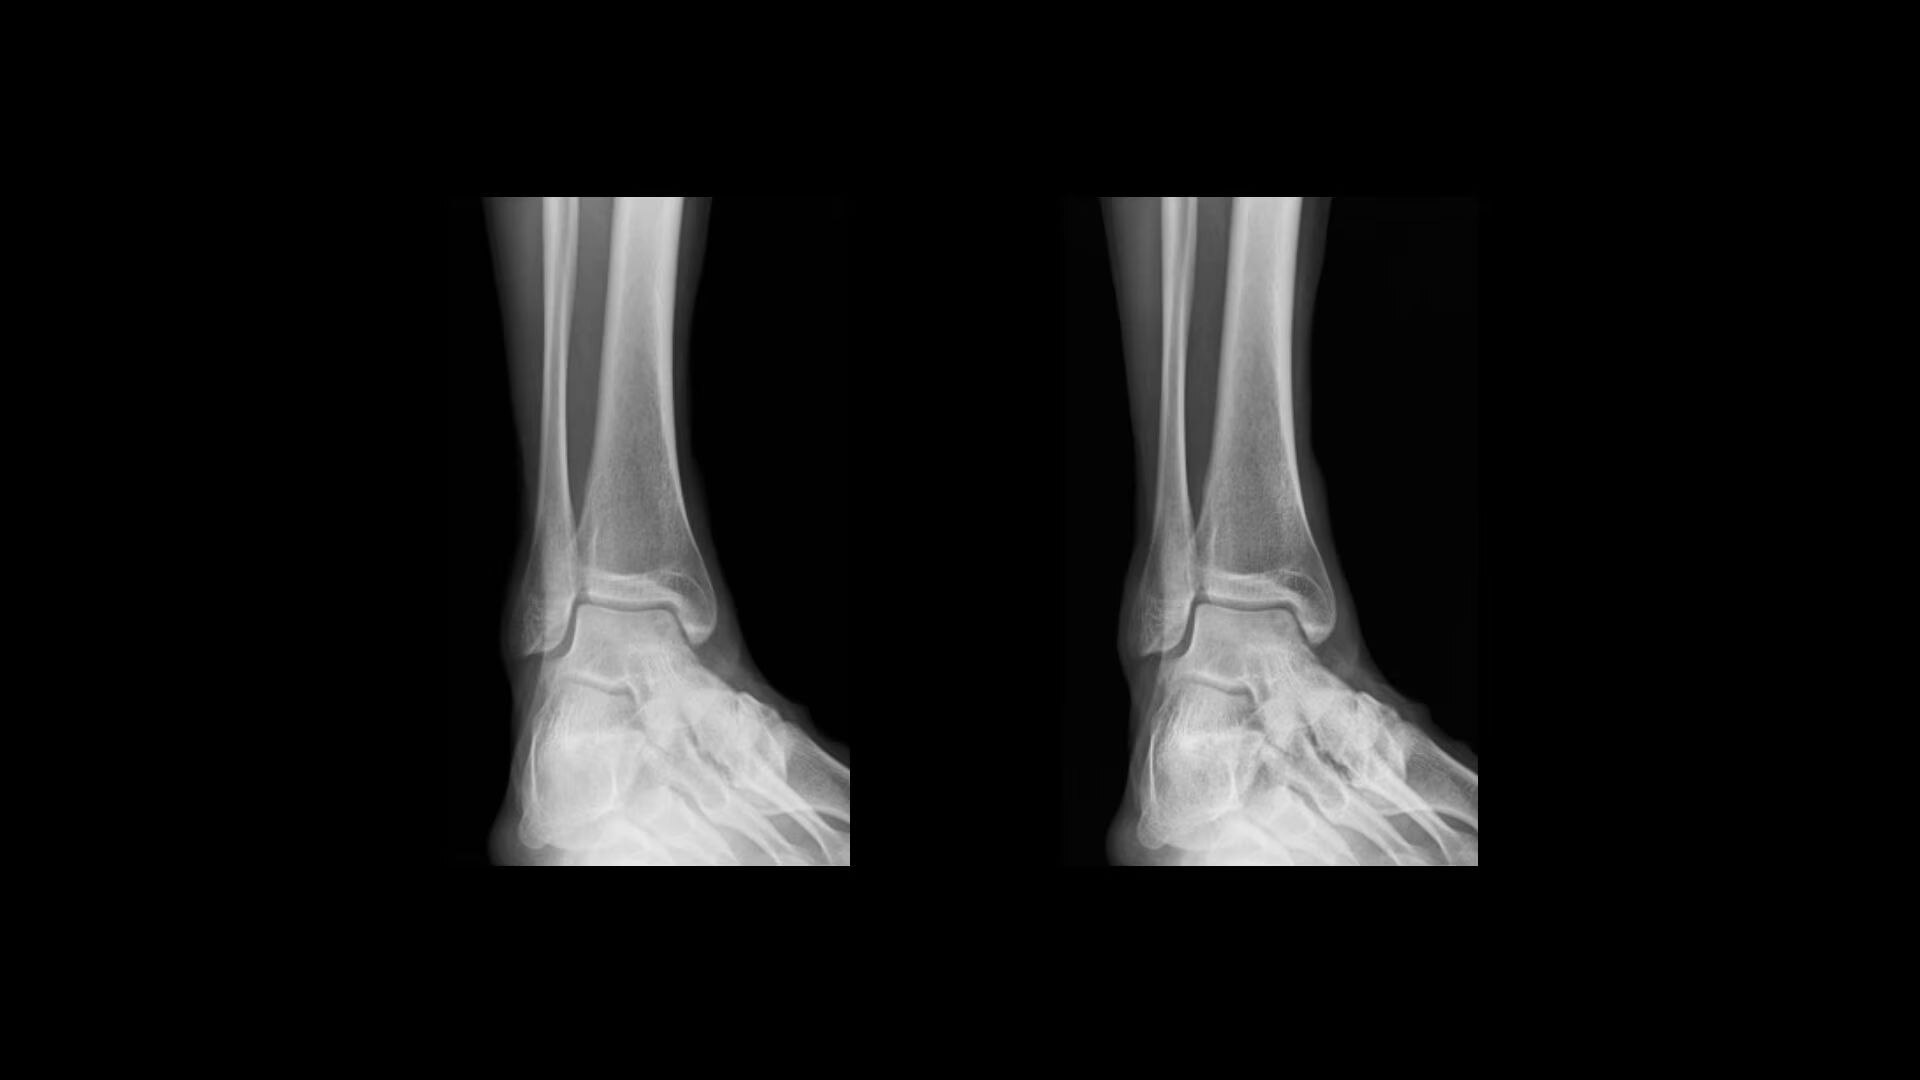

Extraordinary anatomical detail at low dose

The power of Helix Advanced Image Processing, coupled with our FlashPad™ Imaging Suite of detectors, provides uncompromised image quality thanks to ultra-high resolution and enhanced noise control.

Local Contrast Enhancement (LCE) increases local contrast in both pediatric and adult chest X-ray images for better visualization of the lungs, heart, and spine regions. It is also available for ankle joint (AP), foot (AP), and patella (tangential)*, and has three levels of enhancement (low, medium and high).